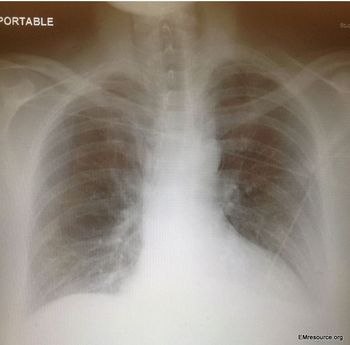

The patient reports the chest pain began 6 days ago during a vacation abroad. She denies any injury. What does the chest x-ray reveal?